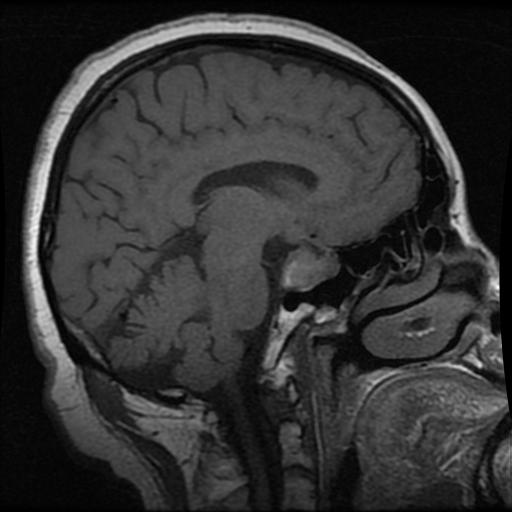

No Tumor

No Tumor

No Tumor

No Tumor